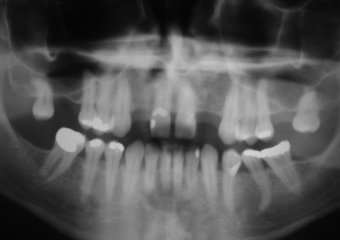

Raio X inicial